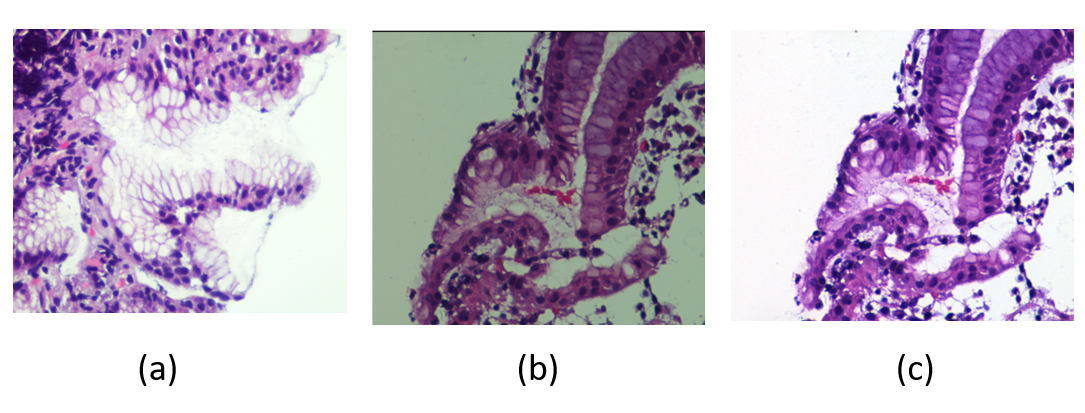

The AE is trained with patches from patients without H. pylori in order to learn a representation space of normality (non-infected tissue) and detect H. pylori as an anomalous staining. We propose to use a shallow architecture without bottleneck, since there are studies [13] that show that non-bottlenecked architectures can be beneficial for anomaly detection. In particular, the proposed AE has 3 convolutional blocks with one convolutional layer, batch normalization and leakyrelu activation. The size of the convolutional kernel is 3 and the number of neurons and stride of each layer are, respectively, [32,64,64] and [1,2,2]. Figure 3 shows the difference in the reconstructions of a non-infected patch, fig.3(a), and a patch with H. pylori, fig.3(b). The reconstruction of the healthy patch looks like the original input image, while the autoencoder has modified the coloration of the tissue in the reconstruction of the patch with H. pylori. In particular, the reconstruction has a color conversion to the blue hue and has lost the brown colored precipitate at the site of specific antibody binding areas associated with the presence of H. pylori. We use this difference in reconstructions to detect the presence of H. pylori as follows.

![]() |

| (a) | (b) |